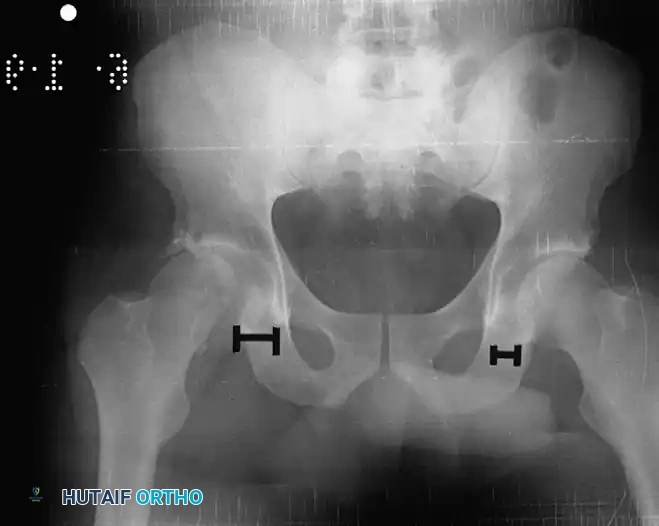

Immediately following closed reduction, a repeat anteroposterior (AP) pelvic radiograph is mandatory to confirm concentric reduction.

Clinical Pearl: Nonconcentric reduction is a subtle but critical finding. It is radiographically identified by a persistent widening of the medial joint space—specifically, the distance between the radiographic teardrop and the femoral head—when compared to the contralateral normal hip.

Fig. 52-45 Widening of the medial joint space after closed reduction indicates a nonconcentric reduction, highly suspicious for entrapped osteocartilaginous fragments or labrum.

If the reduction is concentric, the patient must undergo a high-resolution CT scan of the pelvis with thin (2-3 mm) axial, coronal, and sagittal reformats. CT is vastly superior to plain radiography for identifying intra-articular fragments, subtle acetabular wall fractures, and femoral head impaction injuries.

Fig. 52-46 Axial CT scan clearly demonstrating a retained osteochondral fragment interposed between the femoral head and the acetabular dome. Operative excision is strictly indicated.

CT scan of the pelvis providing detailed visualization of the posterior wall comminution and the relationship of the femoral head to the acetabular columns.